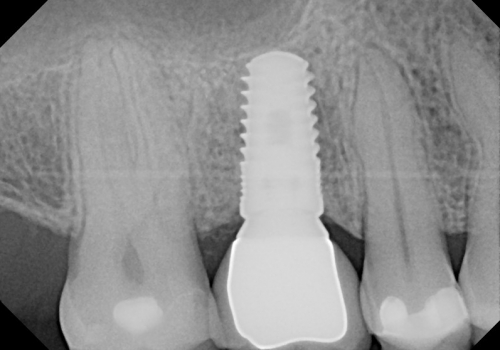

Stomatologiyanın təməl vəzifələrindən biri, itirilmiş dişlərin funksiya və estetik olaraq təbiiyə ən yaxın şəkildə bərpa edə bilməkdir. Dişsizliyin estetik və funksional olaraq yüksək səviyyədə reabilitasiyası, pasiyentlərin çeynəmə, danışma və gülmə kimi funksiyalarını qüsursuz icra edə bilməsi baxımından çox önəmlidir. Diş implantları xüsusi texnologiya hazırlanaraq, itirilmiş dişin bərpası üçün tətbiq edilən süni diş kökləridir. Bu metod təbiiyə ən yaxın bərpanı vəd edən müalicə metodu kimi uzun illərdən bəri beynəlxalq miqyasda geniş tətbiq olunur. İmplantasiya, bu işin peşəkarı yüksək ixtisaslı mütəxəssis tərəfindən qısa bir müddət davam edən prosedur vasitəsilə ağrısız, qısa müddətə və həyati funksiyaların məhdudlaşmaması şərti ilə həyata keçirilən müalicə üsuludur.

Dental implantlar əsasən titandan hazırlanır. Bu materialdan hazırlanmasının ən başlıca səbəbləri, bu metalın orqanizm tərəfindən rədd edilməməsi, heç bir allergik reaksiyaya səbəb olmaması və bu təyinat üçün yetərli möhkəmliyinin olmasıdır. Diş implantları vasitəsilə, tək diş əksikliyindən, çoxsaylı diş əksikliyi və tam dişsizlik halları funksional və estetik bərpa edilə bilir. İmplantın üzərinə hazırlanan diş konstruksiyaları müvafiq vəziyyətlərdə implantların tətbiqi ilə eyni gündə və ya müəyyən bir sağalma dövrünün keçməsindən sonra hazırlana bilir. İmplantların istismar müddəti, doğru planlama və icraat həyata keçirildiyində, eyni zamanda yetərli gigiyenik qulluq şəraitində bir neçə on illik bir periyodu əhatə edə bilir.